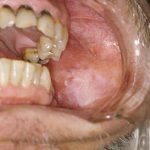

Raised white patches on the inside of the cheek, tongue, or lips. In the mouth, leukoplakia may be due to irritation from poorly fitted dentures, chronic cheek biting, or tobacco. In its early stages, leukoplakia usually causes no symptoms and is diagnosed during the course of a routine physical or dental examination. Because it is a potentially cancerous condition, leukoplakia must be closely monitored by a physician; a biopsy may be necessary. Treatment consists of eliminating all tobacco products and other irritants.

Formation of white spots or patches on the mucous membrane of the tongue or cheek. The spots are smooth, irregular in size and shape, hard, and occasionally fissured. The lesions may become malignant.

A smooth, whitish patch on the oral mucosa that lacks a specific cause such as thrush or any other particular ailment.

White patches in the oral cavity, typically found on the tongue, are commonly known as leukoplakia. This condition is often linked to smoking or the friction caused by a rough tooth or denture. However, the exact factors leading to its occurrence on the vulva remain unknown.

While the elevated patches generally do not cause harm or pain, there are instances where they can undergo a cancerous transformation in the impacted tissue. Due to this potential risk, it is important to always consult a doctor when dealing with leukoplakia.